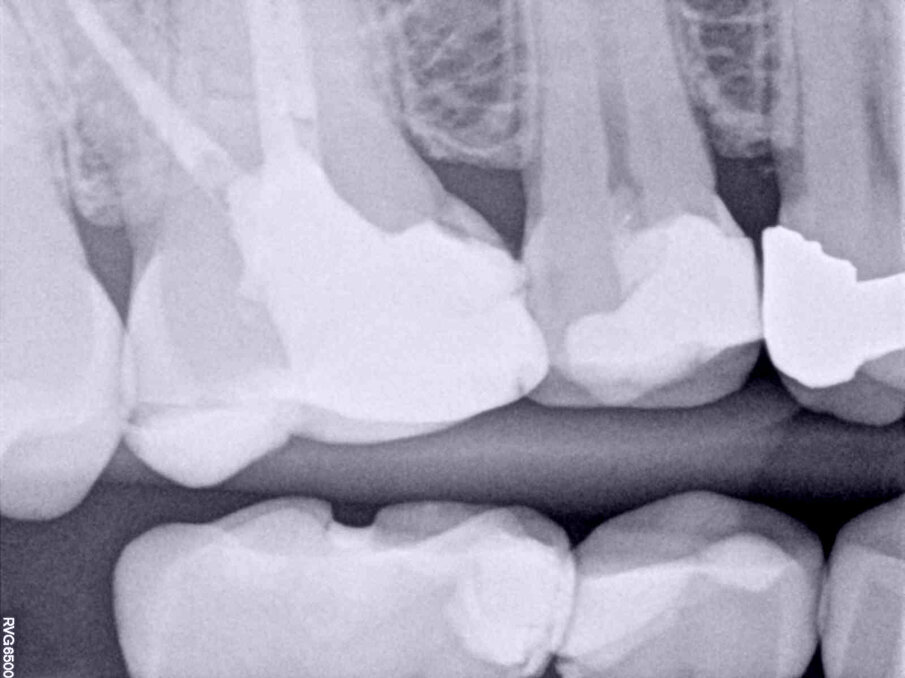

In both cases presented, the root canal therapy was necessary due to an irreversible pulpitis process affecting the respective teeth (Figs. 4a–5b). Both were approached minimally invasively, starting from the endodontic access cavity preparation and finishing with the post endodontic core build-up.

Figs. 4a–d: Root canal therapy performed through a conservative access cavity in a tooth #37 with severe curvatures at the mesial root. The root canal obturation was performed by the hydraulic compaction technique.

One of the most challenging situations when working through conservative openings is the root canal obturation step. The lack of straight line access, compromised visibility and a reduced opening to properly clean the pulp chamber are factors to take into consideration.15 The physical properties of calcium silicate-based endodontic sealers allow clinicians to overcome those challenging aspects. The relatively easy obturation technique, flowability and easy process of cleaning the pulp chamber provide the necessary means for proceeding with the endodontic therapy as conservatively as possible without compromising the prognosis. In the clinical cases presented, the Aurum Blue system (Meta Biomed) was used for the root canal shaping and the calcium silicate-based endodontic sealer CeraSeal (Meta Biomed) was used, applied with the cold hydraulic compaction technique (see video below).